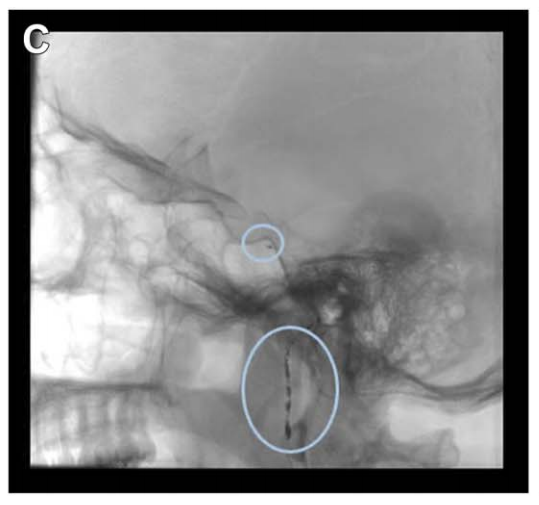

由于该肿瘤血供丰富,福教授在手术前进行DSA检查,显示其主要供血动脉为咽升动脉及脑膜垂体干。为降低后组颅神经损伤风险,选用弹簧圈栓塞技术。栓塞可减少术中出血、软化肿瘤质地,便于手术切除。

诺亚术前栓塞咽升动脉及脑膜垂体干。